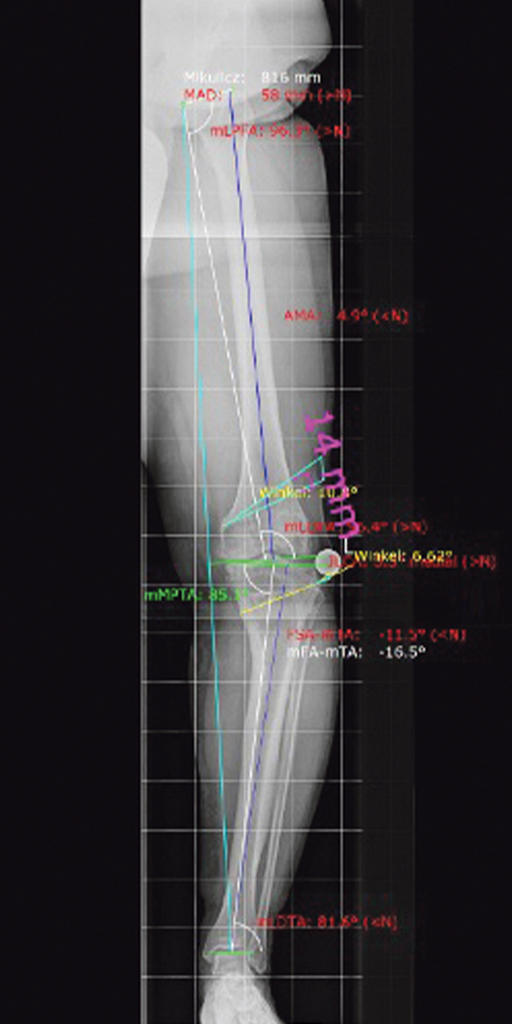

Durch das O-Bein erfolgte die biomechanische Belastung nicht im Zentrum des Kniegelenkes, sondern asymmetrisch weit nach innen verschoben (blaue Linie). Hierdurch zeigte sich schon auf der Innenseite des Kniegelenks eine Arthrose mit einem Grad 4 (Knochen unter dem Knorpel liegt frei) Knorpelschaden. Bei der weiteren Analyse zeigte sich, dass die O-Bein Fehlstellung in einer Deformität im Oberschenkel und Unterschenkel begründet war.

Ganzbeinstandaufnahme vor der Operation

Detailaufnahme